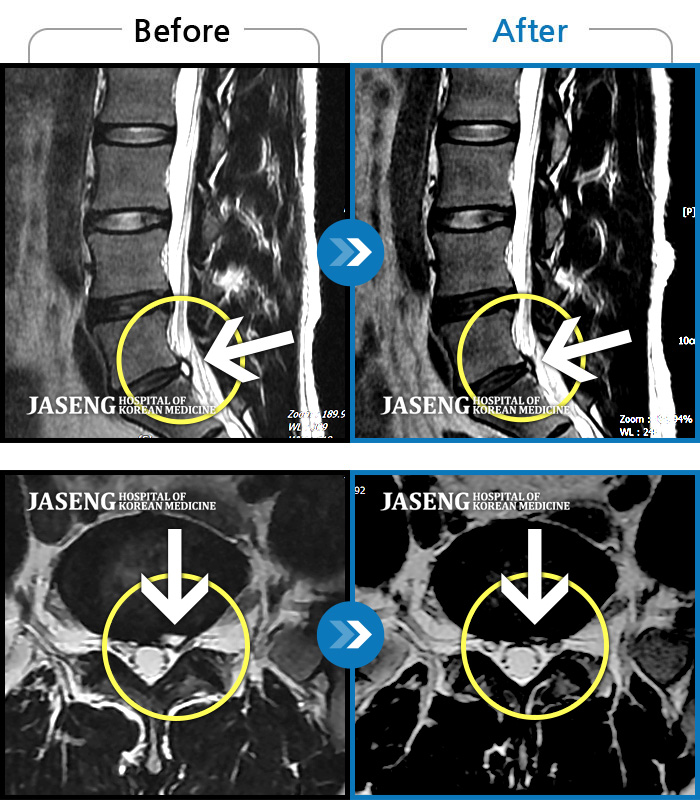

허리디스크

목동 · 고웅 원장

심한 왼쪽 엉치 통증. 종아리, 발바닥 저림

촬영시기

2020.10.14 ~ 2024.10.07

2024.12.24